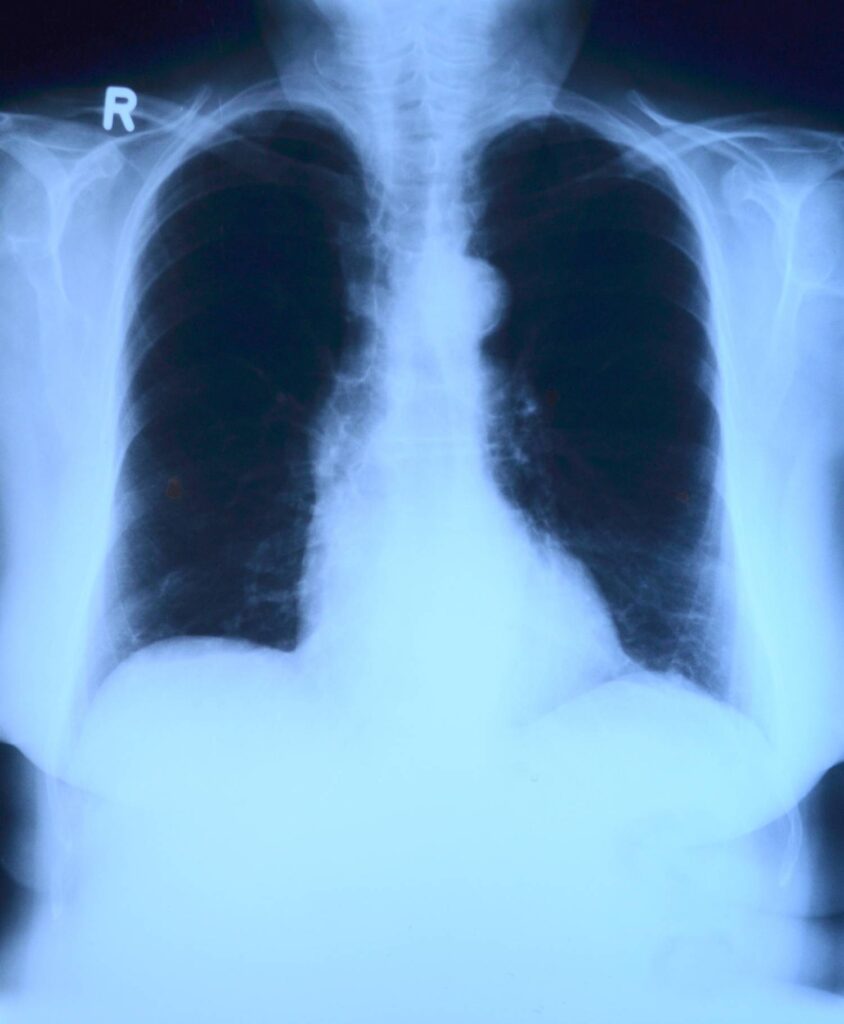

Србија од новембра уводи скрининг за рано откривање рака плућа

У Србији ће новембра почети спровођење организованог скрининга за рано откривање рака плућа. Србија ће постати прва земља Западног Балкана која ће на тај начин дијагностиковати то обољење, речено је данас на конференцији за новинаре у Клиници за пулмологију.

Како је навео, та клиника има апарат за скрининг – „нискодозни скенер“ чија је доза зрачења шест пута мања од стандардног скенера.

На конференцији је речено и да на свака два сата у Србији једна особа умре од карцинома плућа и да статистика показује да се код више од 70 одсто пацијената карцином открије у последњем стадијуму болести, када су шансе за успешно излечење готово исцрпљене.